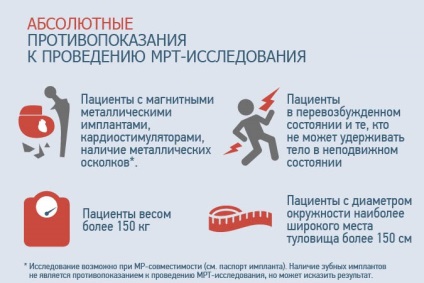

Ellenjavallatai MRI a lumbosacral gerinc megfelelnek a szokásos listáját ellenjavallata tanulmány.

Abszolút ellenjavallatok van a fém implantátumok, állványok vagy elemek a beteg test szöveteiben (műfogsorok, pacemakerek, helyébe fém kötések, osteosynthesis lemezek). Kivételek elemei titánból, mivel a mágneses fém aktivitás minimális.

Terhesség tekinthető relatív ellenjavallat a vizsgálat, de a lehetőség MRI a gerinc az első trimeszterben nagyon ellentmondásos. De a lehetőség a tanulmányok elvégzésére a terhes és szoptató nők döntenek önállóan alapján annak fontosságát, az adatok a nők egészségét.

Ellenjavallatai MRI a gerinc is túlsúlyos (meghaladó megengedett határértékeket a gép - általában 120 kg), a klausztrofóbia (esetleg egy tanulmányt a nyugtatók), súlyos többszervi elégtelenség igénylő hardver karbantartás.